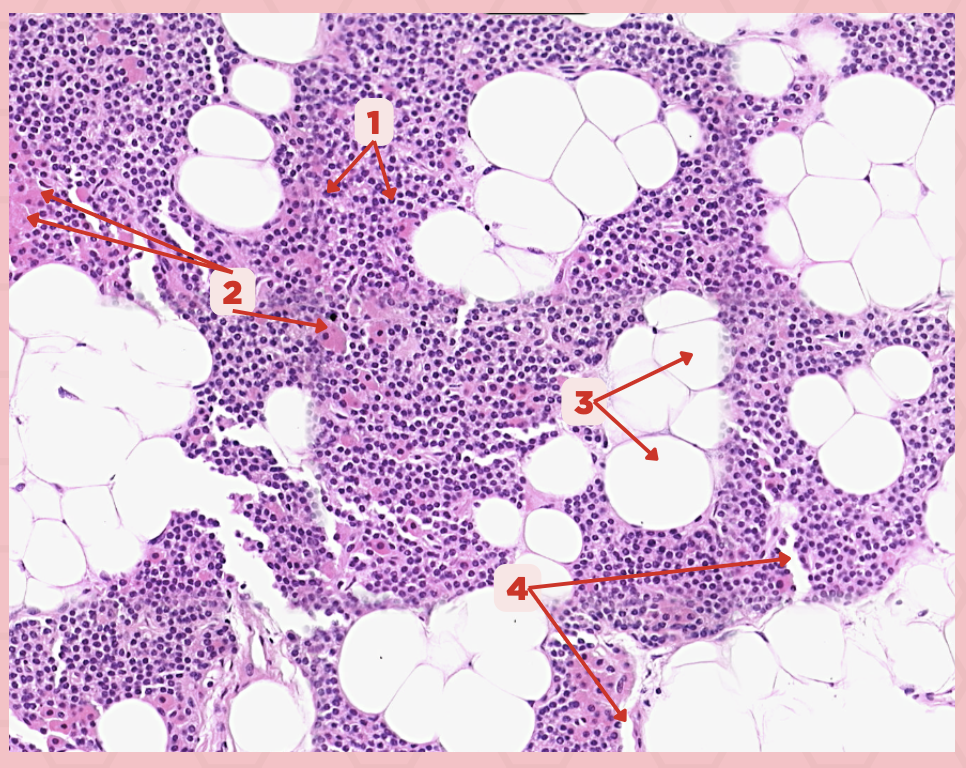

Parathyroid

Identify the specimen.

Chief Cells

Identify the specimen labeled as 1.

Oxyphil Cells

Identify the specimen labeled as 2.

Adipocytes

Identify the specimen labeled as 3.

Capillaries

Identify the specimen labeled as 4.

Newborns

Pointer #2 is hardly present in the parathyroid glands of _____.

Parathyroid

Identify the specimen.